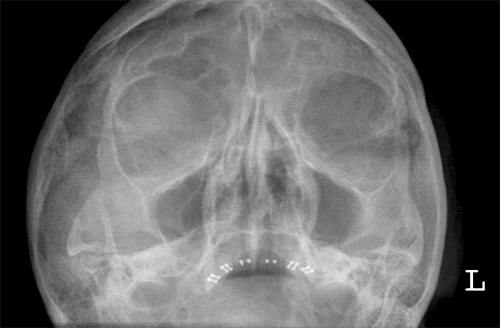

NNH p.a.

Fehler

Projektion der Felsenbeine in die diagnostisch wichtigen unteren Abschnitte der Kieferhöhle, in welchen sich bei einer frischen Sinusitis der Erguss ansammelt (auf der Aufnahme bei sitzendem Patienten!)

Abhilfe

Nasenspitze geringfügig vom Film abheben lassen, mit anderen Worten Kinn mehr vorstrecken; Kopf mehr nach hinten nehmen.